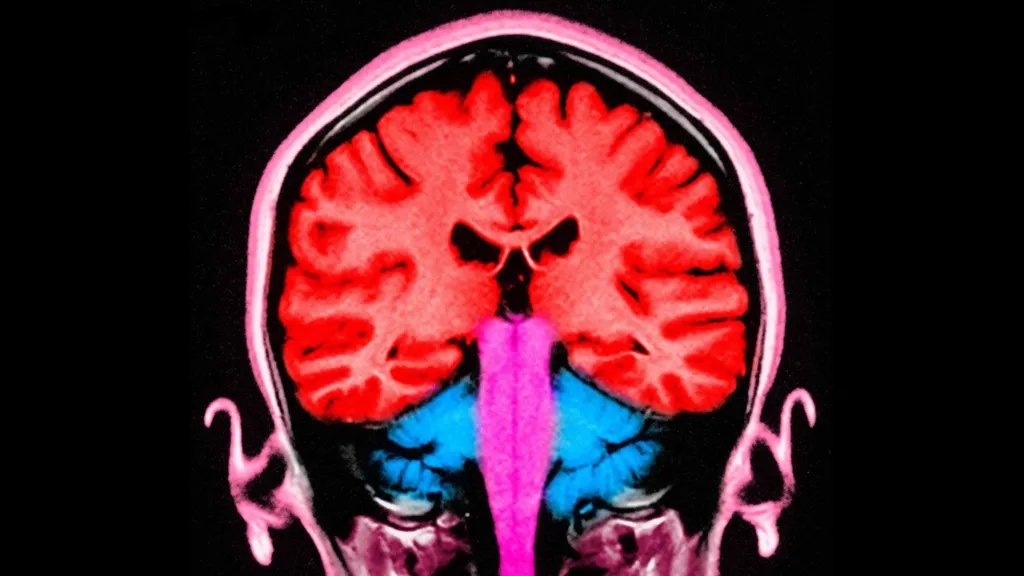

During the experiment, an electrical current was applied to the frontal and parietal areas of the brain - situated at the front and towards the back. When these areas were stimulated at the same time, the participants gave away more money.

In that study, the researchers pinpointed the two brain areas that appeared to be "talking to each other" - with brain cells firing at the same frequency - when players gave away more money.

Those two brain areas are known to play a role in decision-making and in empathy, or distinguishing the feelings of others from our own.

When a more selfless decision was made, the empathy region and the decision region appeared to communicate.